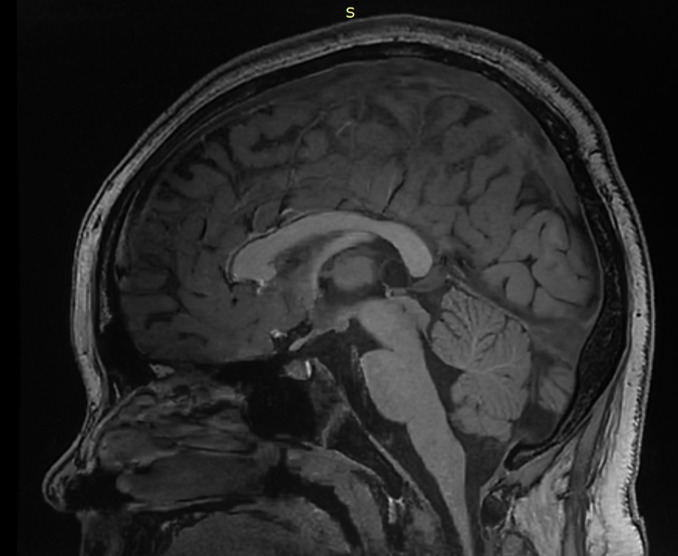

翻譯自MathieuD,Iorio-MorinC.StereotacticRadiosurgeryforPinealRegionTumors.ProgNeurolSurg.2019;34:173-183.doi:10.1159/000493062.作者單位加拿大DivisionofNeurosurgery,DepartmentofSurgery,UniversitédeSherbrooke摘要:松果體區(qū)腫瘤是一組不同組織學實體的異質(zhì)性腫瘤,由于其關鍵部位和頻繁的侵襲行為,治療可能是一個重大挑戰(zhàn)。傳統(tǒng)的治療包括手術切除、分次放療和化療。立體定向放射外科(SRS)正越來越多地用于這些腫瘤的治療。它被用作松果體區(qū)的松果體細胞瘤和乳頭狀腫瘤的主要治療方法,與松果體母細胞瘤和生殖細胞腫瘤的放療或化療相結合,或在腫瘤復發(fā)的情況下作為輔助放療增強劑。報告的發(fā)病率很低,在大多數(shù)情況下包括短暫的動眼神經(jīng)障礙。作為顯微外科切除術的一種非侵入性替代方法,在討論這些具有挑戰(zhàn)性的病例時,應始終考慮SRS。松果體實質(zhì)腫瘤(PPT)PPT起源于松果體細胞,松果體細胞是松果體分泌褪黑素的特殊細胞。世衛(wèi)組織將這些腫瘤分為3個亞型,包括松果體細胞瘤(WHOI級)、中分化PPT(PPTID;WHOII、III級)和松果體母細胞瘤(WHOIV級)。正如預期的那樣,治療和預后高度依賴于腫瘤分級。松果體細胞瘤更常見于年輕至中年成年人。它們是良性病變,完全手術切除可能治愈。然而,對于關鍵部位的其他良性腫瘤,手術與發(fā)病風險顯著相關。越來越多的文獻支持使用SRS作為切除術的微創(chuàng)替代方案。IGKRF系列報告了26名患者,包括24名作為初始治療一部分的SRS患者和2名復發(fā)患者[2]。20年時,累計局部控制率為81%,生存率為76%。Wilson等人[7]對5例次全切除的松果體細胞瘤患者使用SRS(3例為輔助治療手段,2例為腫瘤進展)。平均隨訪65個月后,所有患者均顯示局部腫瘤控制,無并發(fā)癥。Mori等人[3]共治療了6例松果體細胞瘤患者中的13個腫瘤,5年后的PFS為80%。Reyns等人[8]報告了他們對8例松果體細胞瘤患者進行SRS治療的經(jīng)驗。6名患者最初僅接受SRS治療,2名患者接受SRS治療部分切除后的殘余疾病。平均隨訪32個月后,所有患者均存活,腫瘤消退或穩(wěn)定。在他們的文章中,Lekovic等人[6]報道了8例松果體細胞瘤患者的SRS結果。所有腫瘤均在最后一次影像學隨訪中得到控制,隨訪時間為2至56個月。1名患者在SRS后2個月死于無相關原因的腫瘤,該腫瘤在影像學上表現(xiàn)出嚴重退化。圖1描述了一例由原發(fā)性SRS治療的典型松細胞瘤。圖1。一名38歲女性患者因松果體區(qū)腫瘤繼發(fā)于腦積水,表現(xiàn)為復視。她接受了內(nèi)鏡下第三腦室造瘺術和腫瘤活檢。病理證實為松果體細胞瘤。然后,她讓SRS擔任主要治療手段。SRS術后3個月,由于短暫的腫瘤擴張,她的復視暫時惡化。在SRS后的最后36個月隨訪中,腫瘤逐漸消退,臨床上保持穩(wěn)定。PPTID在2007年修訂的WHOCNS腫瘤分類中得到正式認可。它們具有與復發(fā)風險增加相關的組織學特征,通常通過手術切除進行治療。增加分級放射治療或SRS仍然是一個有爭議的問題。在IGKRF系列中,有4名患者在治療前、3名患者在復發(fā)接受SRS治療[2]。SRS后5年的累計局部控制率和生存率分別為50%和56%。在所有其他研究中,分析沒有組織學分層,PPTID的結果與松果體細胞瘤的結果合并在一起,使得比較困難。Park等人[9]報告了9名1級和2級PPT患者的SRS作為主要治療方法。平均隨訪79個月后,所有患者均存活,所有腫瘤均顯示完全或部分緩解。只有1名2級腫瘤患者最終接受了腦脊液播散。Balossier等人[10]還報告了9例1級或2級松果體細胞瘤患者,作為初始治療的一部分,他們單獨或在部分切除后接受SRS治療。所有8名接受影像學隨訪的患者均實現(xiàn)了腫瘤控制,隨訪時間從5個月到76個月不等。Yianni等人[5]報告了11例PPT患者的SRS治療結果(包括6例松果體細胞瘤、3例PPTID和2例松果體母細胞瘤)。他們報告SRS后1年PFS為81%,5年PFS為54%。不幸的是,沒有按照腫瘤分級進行分析,這使得解釋更加困難。據(jù)推測,通過包括松果體細胞瘤,這些研究高估了SRS對PPTID的療效。松果體母細胞瘤是一種高度惡性的腫瘤,通常發(fā)生在兒童和年輕人身上。建議的治療包括最大限度的手術切除,然后分次放療和化療。據(jù)報道,SRS主要出現(xiàn)在復發(fā)的情況下,或作為初級治療后的局部增強治療。IGKRF系列包括13名患者,其中8名患者SRS作為一種加強治療方式,在5例復發(fā)時使用SRS。局部控制和生存率較差,5年累計率分別為27%和48%。作為多模式管理的一部分,Mori等人[3]對2例松母細胞瘤患者的4個腫瘤進行了SRS。2名患者分別在SRS后3個月和13個月出現(xiàn)腫瘤進展。在Reyns等人[8]的研究中,5例松果體細胞瘤患者在手術切除、分割放療和化療的基礎上,還接受了SRS治療。2例患者的病情仍得到控制,2例患者出現(xiàn)局部腫瘤進展延遲,1例局部腫瘤控制患者出現(xiàn)遠處腦播散。2名患者死于腫瘤進展。在他們的系列研究中,Lekovic等人[6]治療了1例復發(fā)性松果體母細胞瘤患者。45個月后,患者仍然活著,在影像學上有一個穩(wěn)定的腫瘤。圖2描述了一名患者的情況,作為多模式初始管理的一部分,她接受了SRS治療。圖2。一名21歲女性患者出現(xiàn)腦積水導致顱內(nèi)高壓綜合征。她接受了內(nèi)鏡下第三腦室造瘺術和腫瘤活檢。病理結果為松果體母細胞瘤。她接受了伽瑪?shù)斗派渫饪浦委?,隨后接受了分次放射治療和化療。診斷90個月后,她仍無疾病,神經(jīng)功能正常。松果體區(qū)乳頭狀腫瘤2007年修訂版將松果體區(qū)乳頭狀腫瘤(PTPR)納入WHOCNS腫瘤分類。它們被認為是由亞鰓器官的特殊室管膜細胞產(chǎn)生的。它們可以被歸類為WHOII級或III級腫瘤,但這兩級腫瘤即使在大體全切除后也有很高的局部復發(fā)傾向。最優(yōu)管理仍然是一個有爭議的問題。前期放射治療或化療尚未證明能降低復發(fā)風險[11]。鑒于局部復發(fā)的高風險,許多作者正在研究SRS的作用。IGKRF研究包括6名PTPR患者[2]。5名患者在組織學診斷后接受SRS作為初始治療的一部分,另1名患者在大體全切除后復發(fā)接受治療。5名患者出現(xiàn)局部復發(fā),導致5年時的累計局部控制率僅為33%。所有這些患者對復發(fā)的腫瘤重復SRS,導致4名患者的局部控制時間延長。5年時的累計生存率為100%。Yianni等人[5]的系列研究包括2名PTPR患者。無法進行長期隨訪,但在SRS后1年,2名患者均顯示腫瘤控制。Balossier等人[10]報告了1例部分切除后出現(xiàn)SRS的患者,術后6個月腫瘤穩(wěn)定。Fauchon等人[11]發(fā)表了文獻中最大的PTPR回顧性隊列,共包括43名患者。只有2名患者在活檢和部分切除后接受了SRS檢查。2名患者在未指定的時間間隔后均出現(xiàn)腫瘤復發(fā),1名患者最終死亡。Shakir等人[12]報告了1例PTPR患者,在部分切除和替莫唑胺化療1年后,補充SRS。腫瘤逐漸消退,9年后仍處于控制狀態(tài)。Riis等人[13]報告的另1名患者在立體定向活檢后出現(xiàn)SRS,并在5年后證明腫瘤持續(xù)消退。Cardenas等人[14]發(fā)表了1例SRS后腫瘤控制7年的患者。當時,他有腫瘤進展,接受了大體全切除術,沒有復發(fā)。圖3顯示了一名年輕患者的情況,該患者作為治療的一部分接受了2次SRS治療她的PTPR。圖3。一名4歲女性患者因松果體區(qū)腫瘤繼發(fā)腦積水。她接受了部分腫瘤切除術,證實了PTPR的診斷。然后她接受SRS作為殘余腫瘤的輔助治療。在接下來的幾個月里,腫瘤立即消退。SRS術后18個月,MRI顯示無癥狀局部腫瘤復發(fā)。她對復發(fā)的腫瘤進行了重復SRS治療,隨后出現(xiàn)完全的腫瘤反應,在最后一次手術后的88個月的最新隨訪中仍持續(xù)穩(wěn)定。其他腫瘤松果體區(qū)可出現(xiàn)腦膜瘤、膠質(zhì)瘤和轉(zhuǎn)移瘤。由于它們的影像學特征,診斷這些病變通常很簡單。SRS通常用于其他部位的腫瘤治療,具有可預測且眾所周知的反應特征。SRS治療這些腫瘤的主要考慮因素是限制對鄰近腦干的劑量,以降低輻射誘發(fā)毒性的風險。討論關于SRS在松果體區(qū)腫瘤中的應用的文獻仍然有限,并且很難從現(xiàn)有發(fā)表的研究中得出有意義的結論。其中一個主要原因是,為了補償有限的患者數(shù)量,作者必須將不同的腫瘤組織學亞組匯總在一起,從而得出可能不適用于所有特定腫瘤的局部控制和生存數(shù)據(jù)[3,5,6,15]。IGKRF最近發(fā)表的研究試圖通過組織學分層分析來緩解這一事實,從而提供更好的質(zhì)量數(shù)據(jù)來指導患者管理[2]。然而,現(xiàn)有的文獻已經(jīng)證明,SRS對于某些松果體區(qū)患者是一種有用的治療方式腫瘤。對于生殖細胞瘤,SRS的主要興趣在于它能夠為腫瘤床提供適形放射增強,從而允許使用低劑量的分次放射治療,或在復發(fā)時使用。在非生殖細胞瘤的生殖細胞腫瘤(NGGCT)的情況下,SRS可作為局部增強劑,用于切除術后殘余腫瘤,結合分次放療和化療,或在復發(fā)的情況下。這似乎也是松果體母細胞瘤患者的主要適應癥。在大多數(shù)已發(fā)表的研究中,對于松果體細胞瘤,SRS似乎可以誘導長期的腫瘤生長控制。因此,將預先SRS作為腫瘤切除的替代方案作為主要管理方式似乎是合理的。這可能也適用于PPTID,盡管在許多研究中,由于其與WHOI級腫瘤的分組,這些病變的文獻很難分析??梢钥紤]增加分級放射治療,尤其是在III級腫瘤中。最后,對于PTPR患者,SRS似乎是一種合理的主要治療選擇,因為即使是患有各種組織學腫瘤的患者,SRS也有局部復發(fā)的趨勢。圖4給出了一個建議的SRS整合算法,用于松果體區(qū)腫瘤的治療。圖4。針對組織學證實為松果體區(qū)腫瘤的患者提出的管理流程。在大多數(shù)研究中,與SRS相關的并發(fā)癥是合理的,與手術切除相比是有利的。在IGKRF研究中,28%的病例出現(xiàn)了影像學上輻射引起的變化[2]。15%的患者出現(xiàn)臨床惡化,其中9%出現(xiàn)新的局灶性缺損,7%出現(xiàn)新的Parinaud?綜合征,3%出現(xiàn)腦積水。Park等人[9]報告,接受SRS治療的9名PPT患者中有1名出現(xiàn)暫時性記憶障礙。Yianni等人[5]在他們的44名不同組織學腫瘤患者隊列中,只有一例SRS后出現(xiàn)短暫性復視。在使用SRS治療的13例PPT中,Reyns等人[8]報告了3名患者出現(xiàn)了新的暫時性復視,只有1名患者出現(xiàn)了新的永久性復視。Amendola等人[15]報告,在20名患有各種松果體腫瘤的患者隊列中,沒有SRS相關的并發(fā)癥。在另一組17例不同組織學診斷的患者中,未發(fā)現(xiàn)與SRS手術相關的并發(fā)癥[6]。由于事件數(shù)量和接受治療的患者總數(shù)較少,沒有變量與發(fā)病風險增加相關。在大多數(shù)研究中,腫瘤的邊緣劑量在10-20Gy之間變化。根據(jù)有限的可用文獻,無法提出正式的劑量建議。由于SRS通常用于輔助治療或之前的分次放療后,因此建議相應地調(diào)整劑量,并將腦干的劑量保持在可耐受的范圍內(nèi)似乎是合理的。如前所述,松果體區(qū)腫瘤的治療,包括SRS的使用,應根據(jù)具體的組織學診斷進行調(diào)整。因此,只要可行,應盡一切努力獲取腫瘤組織。然而,這可能并非在所有情況下都可行,因為患者共病、拒絕手術或手術后可用組織有限。IGKRF研究包括10名僅基于影像學診斷的SRS患者,無組織學證實[2]。累計局部控制率和5年生存率分別為61%和67%,與整個系列的匯總結果相似。Li等人[16]報道了一個大系列,包括147名僅基于影像學和臨床診斷的松果體病變SRS患者。他們報告了69%的病例出現(xiàn)了最初的腫瘤消退,在SRS術后1年、3年和5年仍然存活的患者中,局部控制率分別為97%、94%和91%。1年、3年和5年的生存率分別為80%、72%和67%。這些結果似乎支持在選定的患者中使用SRS,即使沒有病理證實。在這些情況下,管理應基于基于所有其他特定患者信息的最有可能的診斷,如果認為必要,應提供適當?shù)妮o助治療(在這種情況下,建議的管理流程見圖5)圖5。針對組織學未知的松果體區(qū)腫瘤患者提出的管理流程結論鑒于松果體區(qū)腫瘤的罕見性,可用于指導治療的證據(jù)水平較低。在現(xiàn)有研究的范圍內(nèi),SRS似乎是一種安全的方式,其有效性和作用取決于組織學。對于松果體細胞瘤和PTPR的主要治療,SRS可以作為手術的合理替代方案,后者更容易復發(fā)。對于生殖細胞腫瘤和松果體母細胞瘤,SRS可以在復發(fā)時使用,也可以作為多模式初級治療的一部分,作為一種輔助手段,減少分次放射治療的劑量。作為顯微外科切除術的一種非侵入性替代方法,在討論這些具有挑戰(zhàn)性的病例時,應始終考慮SRS。(圖:山東大學第二醫(yī)院神經(jīng)外科配置的?LeksellGammaKnifePerfexion)